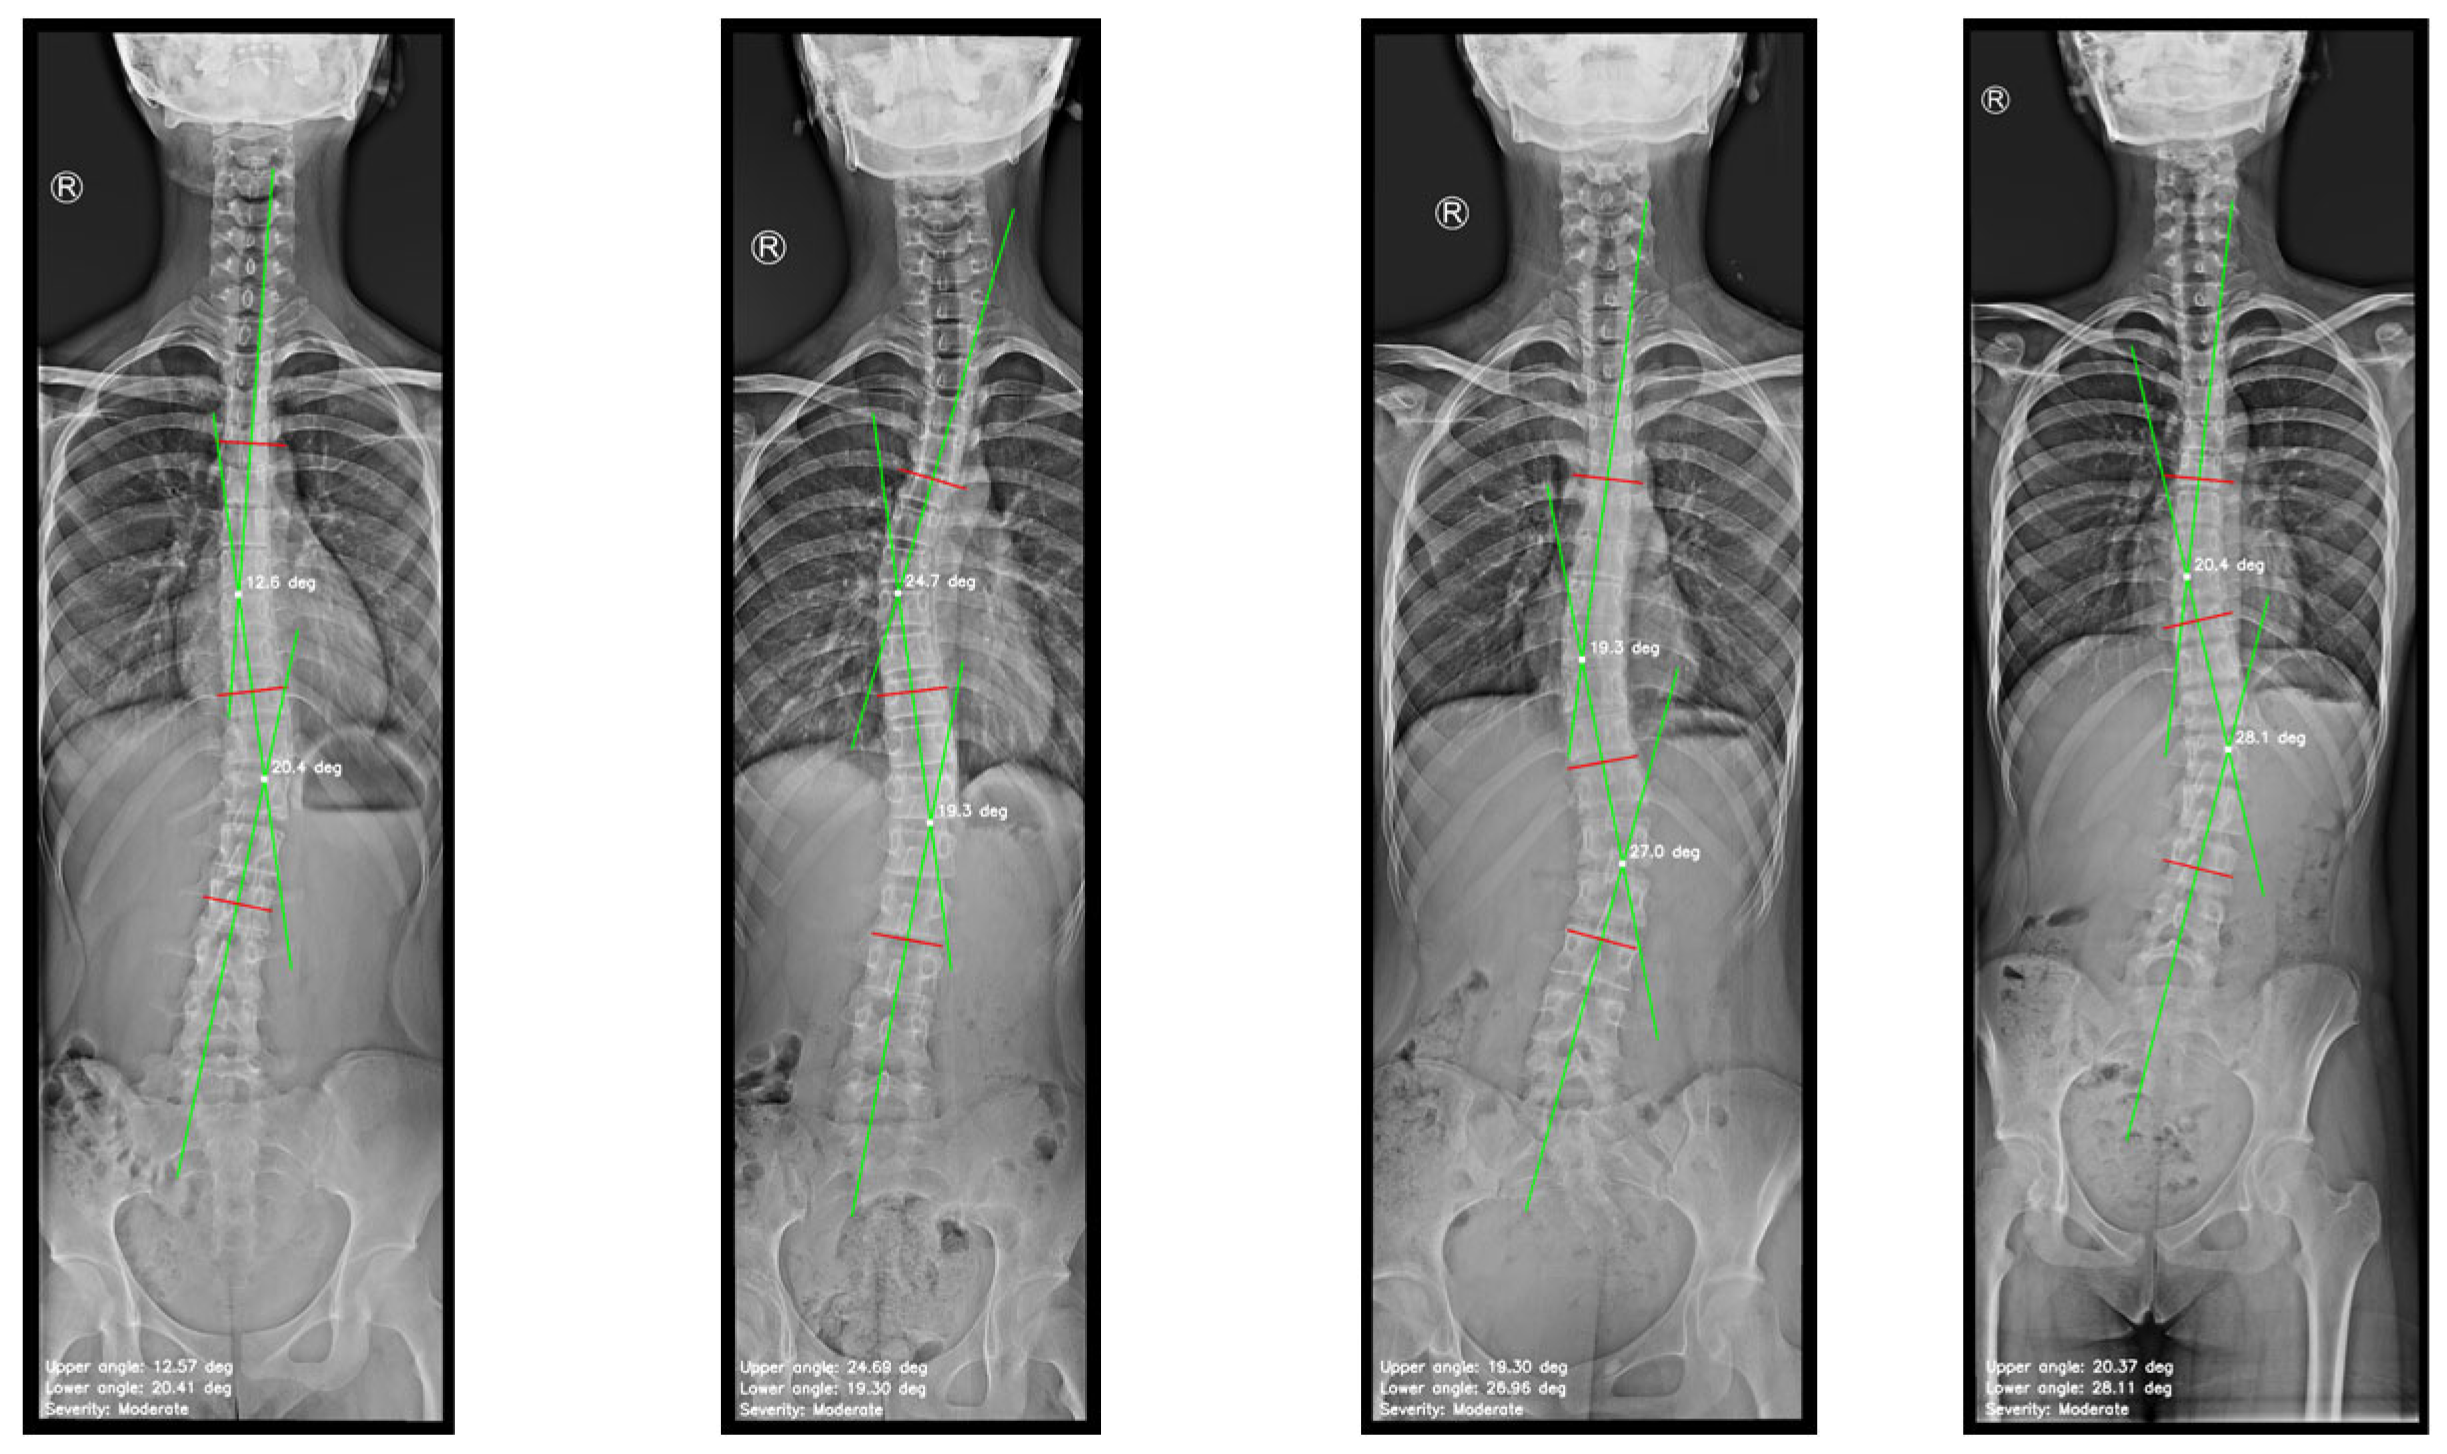

- Figure 7d depicts spinal curve estimation and Cobb angle calculation, based on the analysis of the curvature. The algorithm swipes the curvature and identifies the key anatomical landmarks following their definition: tilted vertebrae are defined as the vertebrae with the greatest inclination angle. They represent the greatest spinal deviation. Apex points correspond to the locations where the spinal curvature reaches its maximum deformation; that is, the points with the greatest lateral displacement relative to a vertical reference line. In our study, this reference is defined as the vertical line drawn from the upper reference point. It is important to note that when the algorithm addresses complex curvatures, two apex points are detected, one on the left (corresponding to negative distances), and one on the right (corresponding to positive distances). The algorithm was designed with a logic to distinguish the type of the curvature, simple or complex, in order to detect the correct number of tilted vertebrae and apex points, to provide either a single Cobb angle measurement or separate upper and lower Cobb angle measurement. The apex point, which refers to the peak of the spinal deviation, is critical for scoliosis assessment. To emulate the manual method, the most tilted vertebrae are isolated and represented on the image, remarked with red lines. Then, the algorithm draws perpendicular green lines from the midpoints corresponding to the most tilted vertebrae and connects them, as performed by clinical experts. The algorithm identifies the intersection point between these green lines, and the angle formed at their intersection is calculated. The Cobb angle and the severity classification are annotated on the image.